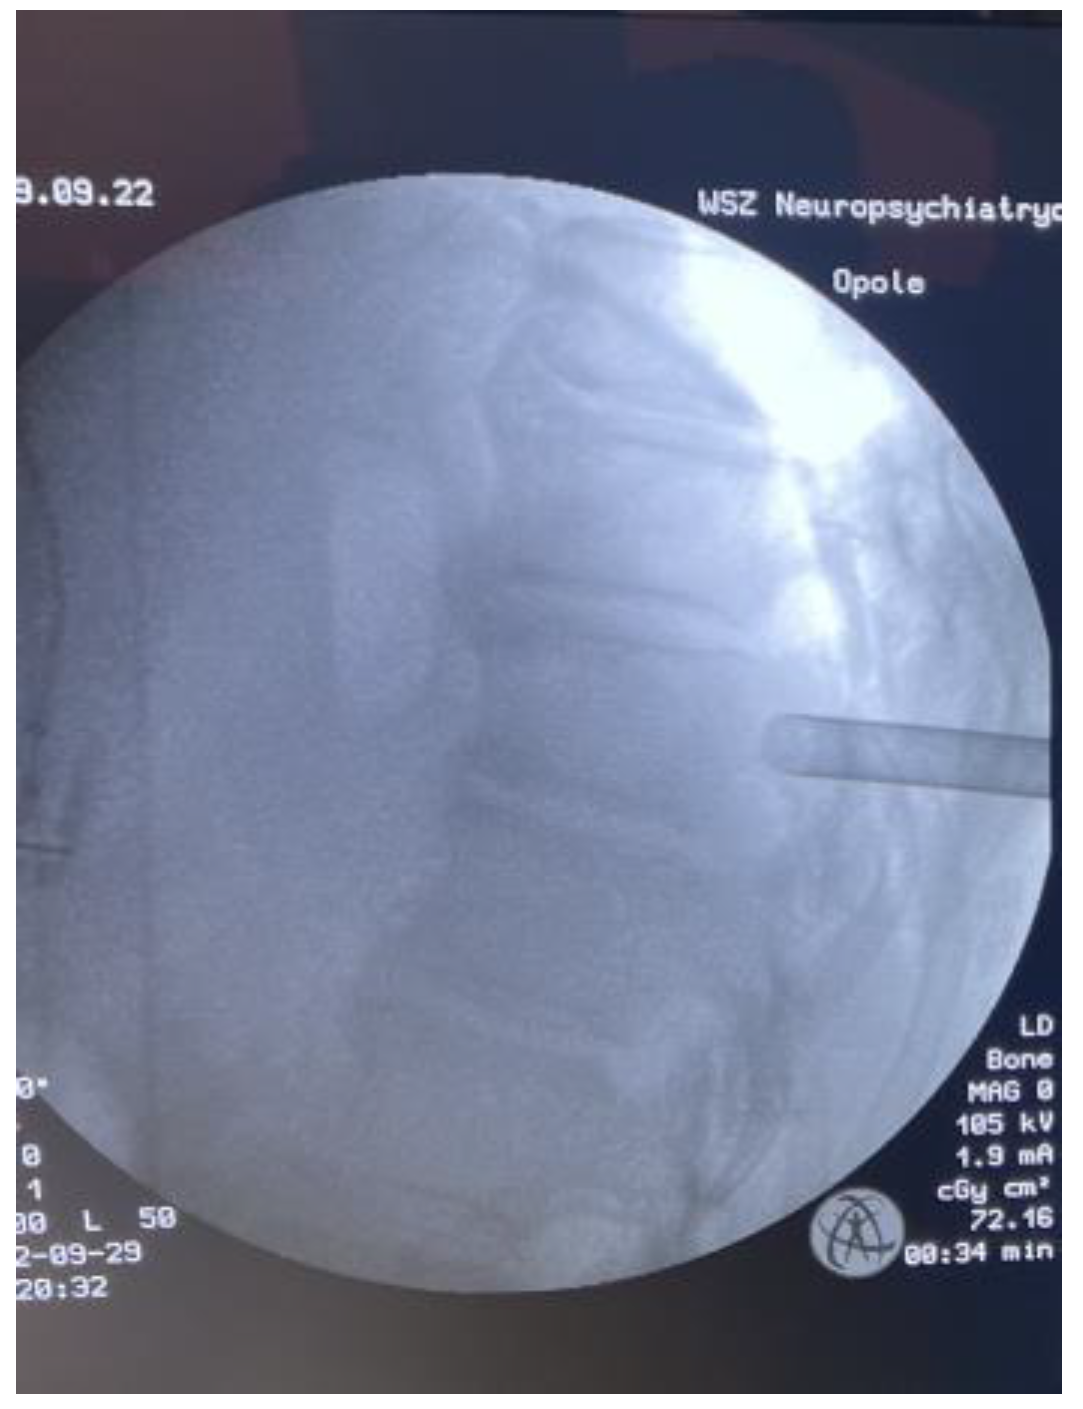

Fully Endoscopic Spine Separation Surgery in Metastatic Disease—Case Series, Technical Notes, and Preliminary Findings

3. Results